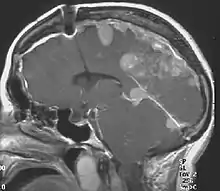

| Figure of various morbidities associated with neurofibromatosis type II.[1] | |